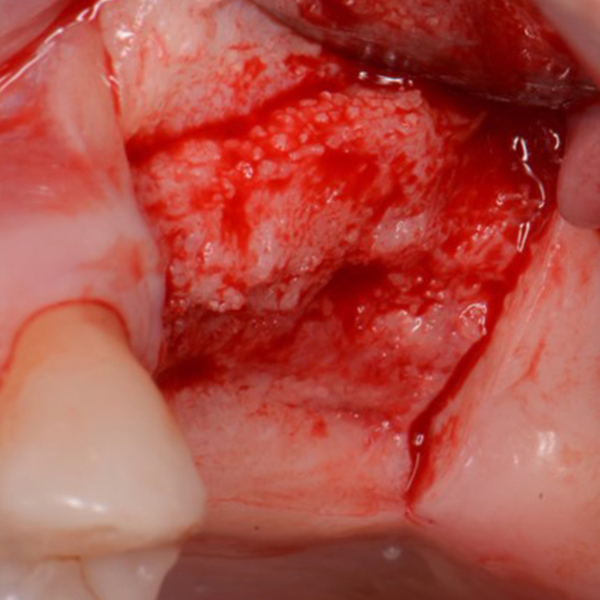

UL5 Extraction and Implant Placement

Patient suffered from a root fracture. Needed removal and to restore hard and soft tissue.